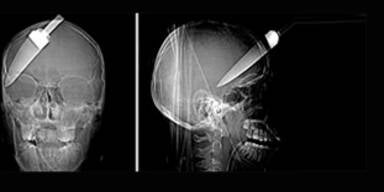

Es ist ein Wunder: Ein 16-jähriger Brite überlebte einen brutalen Angriff - ihm wurde ein Küchenmesser in den Kopf gerammt.

Einem 16-jährigen Teenager wurde ein fast 13 cm langes Küchenmesser in den Schädel gerammt, als er an einer Londoner Bushaltestelle einen Raubüberfall auf einen Bekannten verhindern wollte. Der junge Mann schritt zusammen mit zwei Kameraden beherzt ein - und wurde von den Dieben mit dem Messer attackiert. Ihm rammten sie das Messer in den Schädel, der zweite Bekannte erlitt eine Rückenverletzung, der Dritte wurde an der Schulter getroffen.

Der junge Mann überlebte die schwere Kopfverletzung nur, weil er sofort in ein Spital eingeliefert und einer Notoperation unterzogen wurde. Zehn Monate wurde er entlassen, und besuchte wieder die Schule.